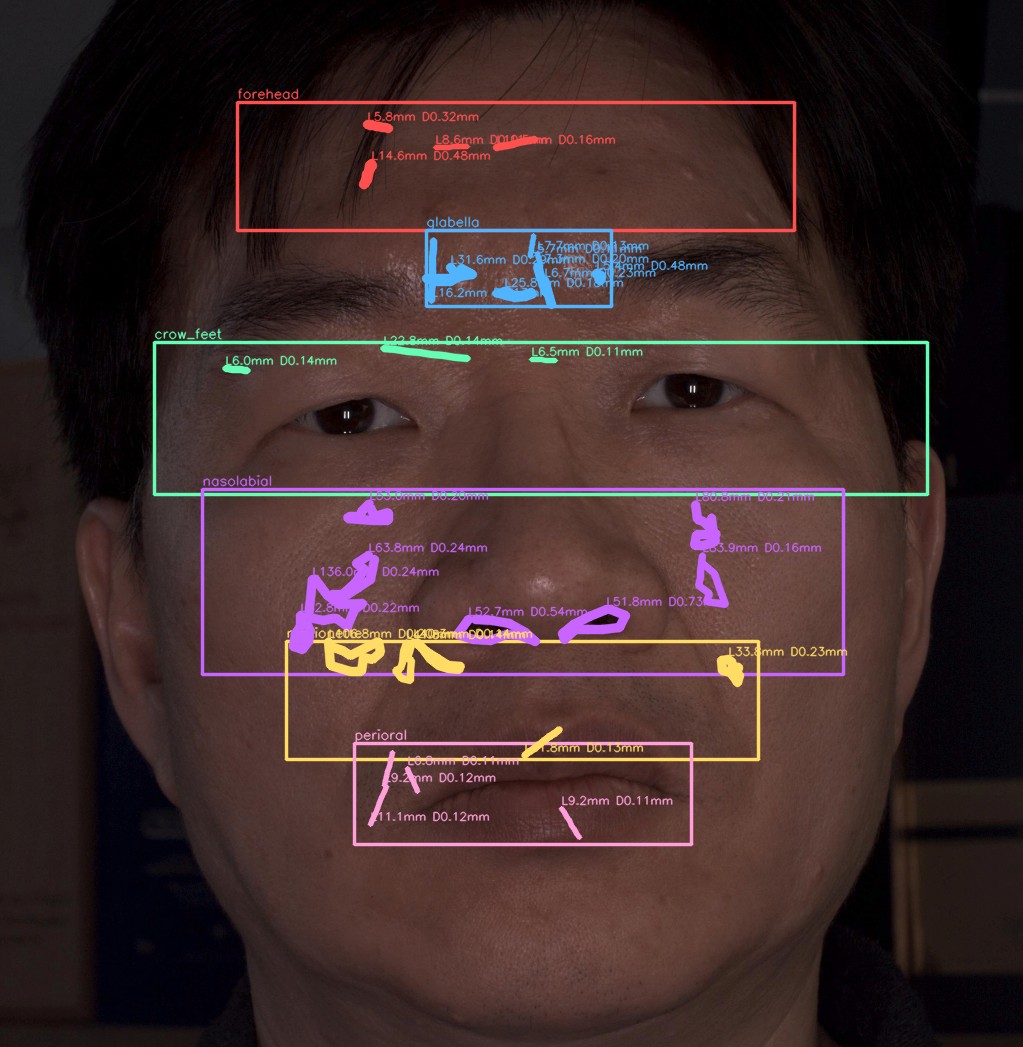

이마

유효 주름 수 4개 · 주 방향 가로

상위 깊이(평균 상위3) 0.320 mm

| # | 길이(mm) | 깊이(mm) | 유효 판정 근거 |

|---|---|---|---|

| 1 | 8.63 | 0.110 | 대표 깊이 0.110 mm가 이 부위 최소 깊이 0.100 mm 이상이고, 유효 길이 8.63 mm가 최소 길이 5.00 mm 이상이어서 노이즈·미세선과 구분되어 유효 주름으로 집계되었습니다. |

| 2 | 10.47 | 0.161 | 대표 깊이 0.161 mm가 이 부위 최소 깊이 0.100 mm 이상이고, 유효 길이 10.47 mm가 최소 길이 5.00 mm 이상이어서 노이즈·미세선과 구분되어 유효 주름으로 집계되었습니다. |

| 3 | 5.76 | 0.322 | 대표 깊이 0.322 mm가 이 부위 최소 깊이 0.100 mm 이상이고, 유효 길이 5.76 mm가 최소 길이 5.00 mm 이상이어서 노이즈·미세선과 구분되어 유효 주름으로 집계되었습니다. |

| 4 | 14.61 | 0.477 | 대표 깊이 0.477 mm가 이 부위 최소 깊이 0.100 mm 이상이고, 유효 길이 14.61 mm가 최소 길이 5.00 mm 이상이어서 노이즈·미세선과 구분되어 유효 주름으로 집계되었습니다. |